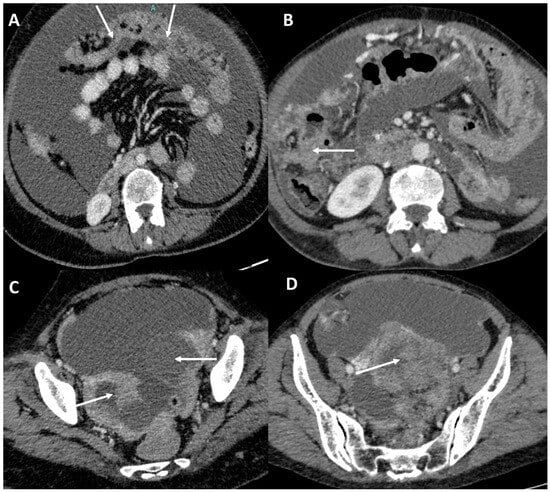

3.4. Peritoneal Involvement

3.5. Predictors of Peritoneal Carcinomatosis